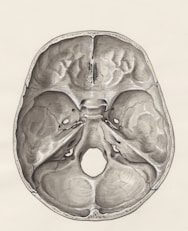

Bariera krew–układ nerwowy

Mózg jest chroniony przez potężne bariery (w tym barierę krew–mózg), których zadaniem jest blokowanie toksyn — w tym bilirubiny.

Wcześniejsze teorie skupiały się na pytaniu, czy bariery te mogą stawać się „nieszczelne”. Badania rzeczywiście sugerują, że wysokie poziomy bilirubiny niesprzężonej mogą uszkadzać integralność tych barier, a czynniki takie jak stan zapalny czy dysfunkcja jelit mogą ten proces nasilać.

Jednak to, czy bariera jest nieszczelna czy pozornie nienaruszona, może nie być kluczowe.

Znacznie ważniejszy jest ten fakt: